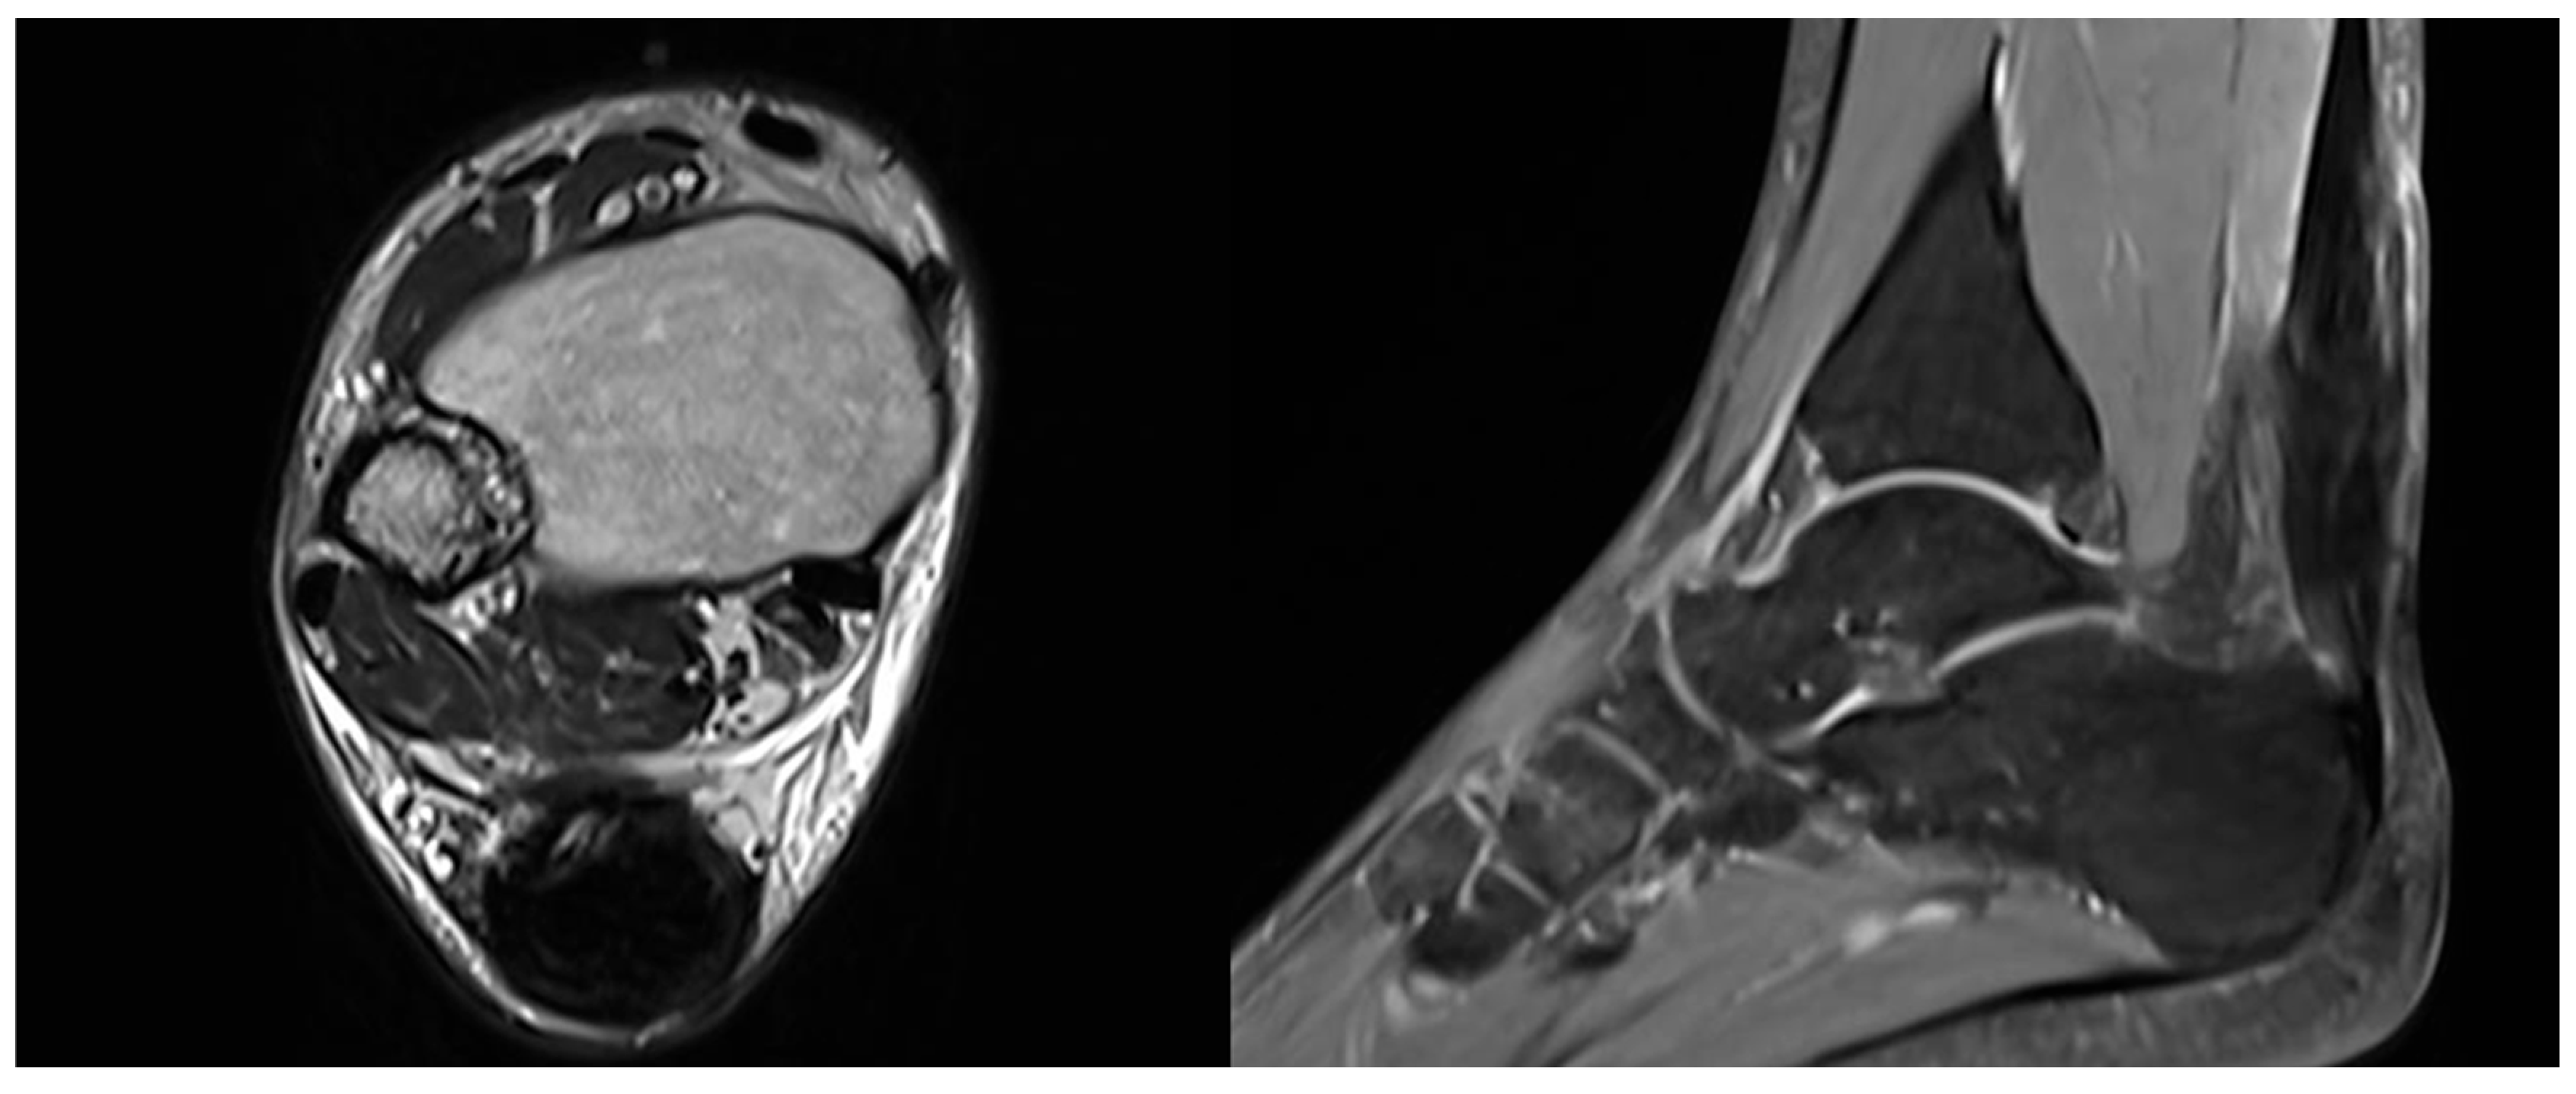

An MRI was performed between 3 and 4 months postoperatively to assess the repair and confirm radiological healing. The images showed signs of tendon healing, with a significant increase in tendon thickness compared to the preoperative condition (Figure 5).

Figure 5. Postoperative MRI at 3/4 months after surgery showing progressive formation of new tendon-like tissue with improvement of tendon thickness.